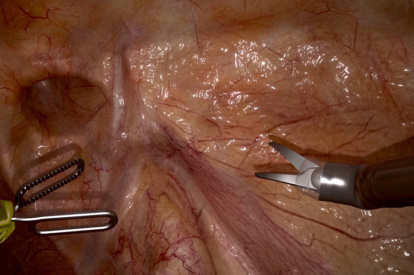

- Highly realistic graphics of human anatomy and simulation of tissue response to instruments

- Complication management: simulation of errors and bleedings

Robotic Cholecystectomy Module

Inguinal Hernia Module

Robotic Prostatectomy Module

Right Hemicolectomy Module

Lobectomy Module